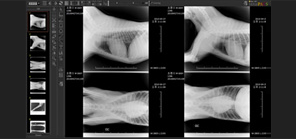

• 다중영상분할 시스템

• 독립된 PACS Viewer를 여러 번 실행할 수 있는 멀티태스킹 시스템 구축

• 한 번에 여러 환자의 영상을 비교 확인 가능